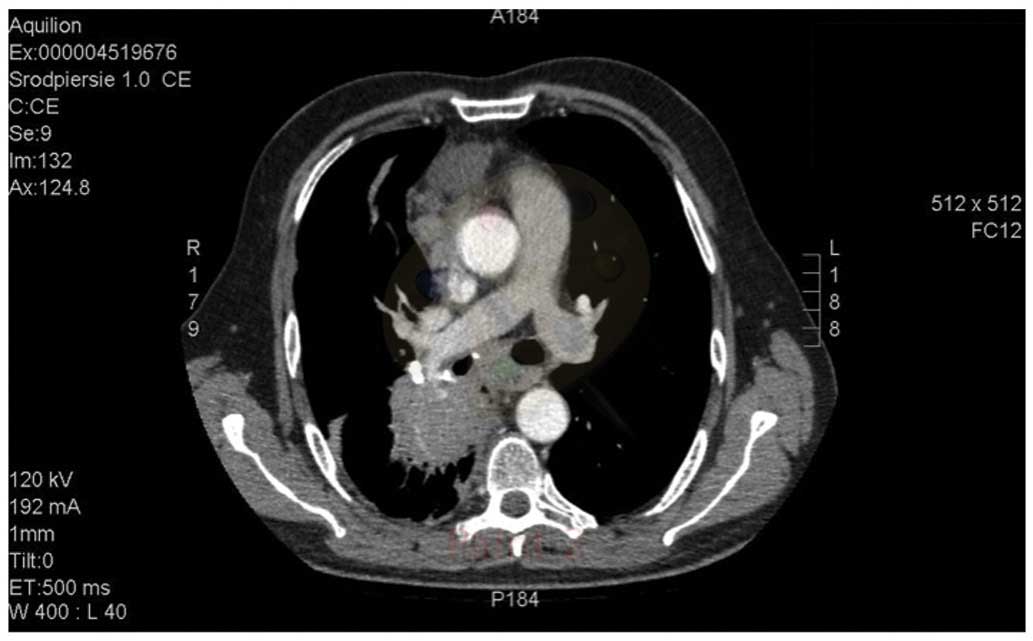

Bradycardia as a rare symptom of cisplatin cardiotoxicity: A case report

Cisplatin (DDP) is one of the most frequently used chemotherapeutic agents, and has a characteristic toxicity profile. For DDP, complications affecting the cardiovascular system, which are typical for certain other agents, are rare; however, their occurrence may lead to life‑threatening conditions. To the best of our knowledge, there are few reported cases of DDP‑induced bradycardia in the relevant medical literature. The current report presents the case of a 58-year-old patient diagnosed with metastatic neuroendocrine carcinoma with a primary lesion in the posterior mediastinum, who was treated with DDP and etoposide chemotherapy. Following the initial chemotherapy cycle, the patient experienced severe symptomatic bradycardia (a drop in heart rate to 40 bpm), with the corrected QT interval prolonged to 424 msec. The patient's condition required close monitoring and treatment. Similar symptoms occurred following each of the three cycles of chemotherapy. Imaging studies performed following the third treatment cycle revealed disease progression, and the patient was referred for palliative care. Reports have indicated that damage to the cardiovascular system, including cardiac ischemia, diastolic disturbances, hypertension and microalbuminuria, may be associated with DDP‑based therapy. However, the mechanism of DDP‑associated cardiac toxicity remains to be elucidated. It may be induced by factors including direct toxicity, ion imbalance, heart infiltration and, in the case of neuroendocrine tumors, the influence of tumor excretions.

Figure 1

Figure 2